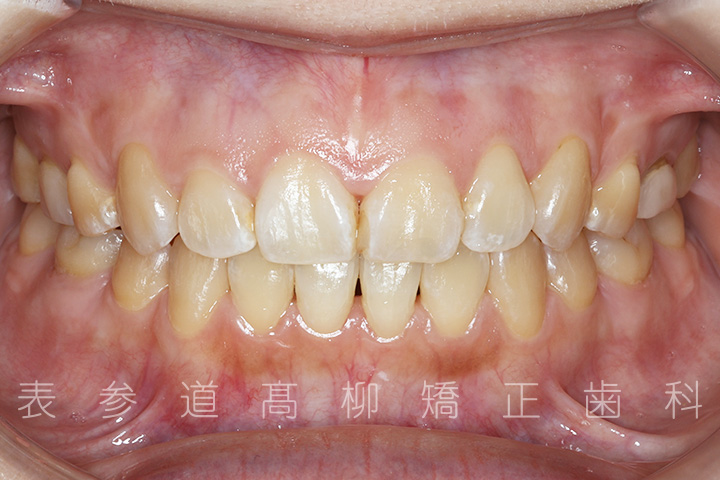

前歯のガタガタ感と開咬でお悩みの患者様の症例をご紹介いたします。

治療前→治療後

術前術後の比較